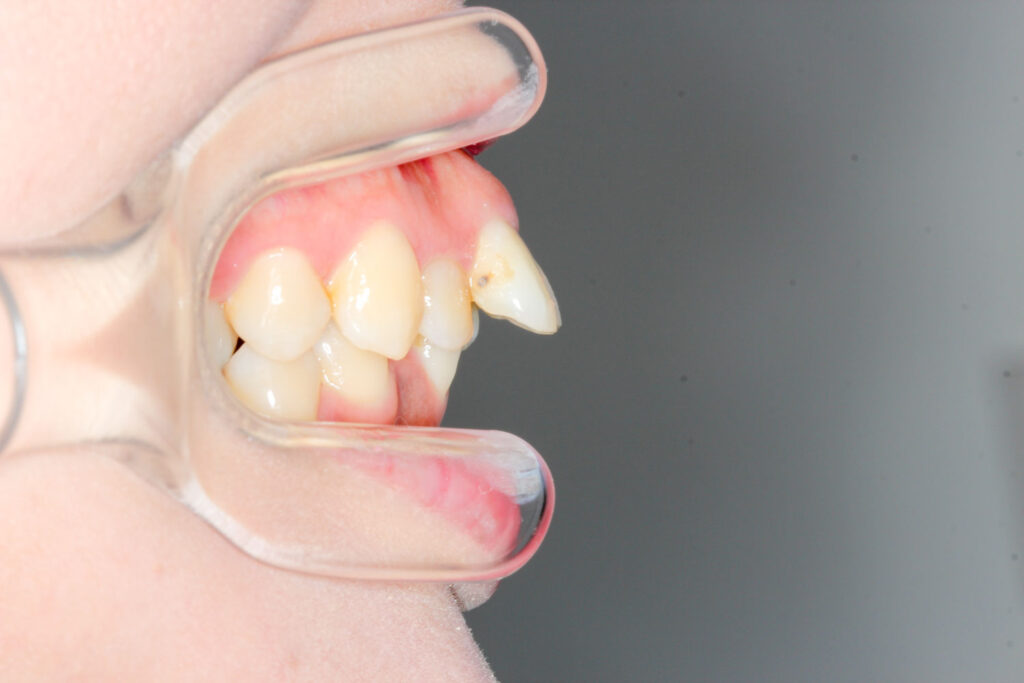

Before

年齢 10代

治療装置 上下とも裏側の矯正装置(フルリンガル)

治療内容 非抜歯

治療期間 2年8か月

リスク 歯の移動に伴う痛み、歯肉退縮、歯根吸収、歯肉炎、虫歯

主訴 八重歯が気になる

症状 叢生(ガタガタ)

治療回数 35回程度

総額費用 140万円程度